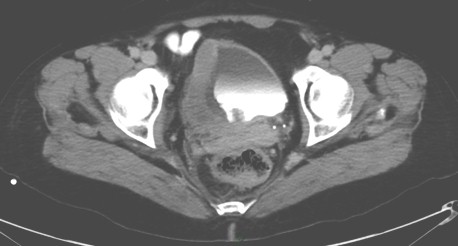

Figura 1: Engrosamiento de la pared inferolateral derecha de la vejiga urinaria.